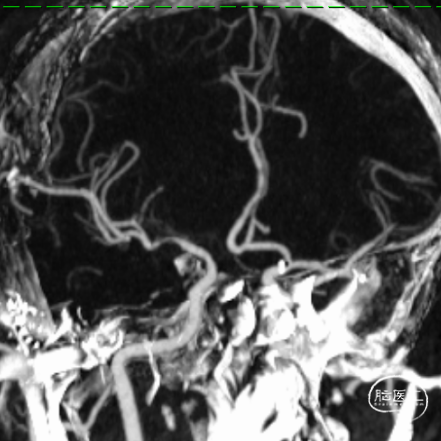

术前造影提示:左侧大脑中动脉闭塞,可见部分豆纹动脉显影,左侧大脑前动脉通过脑膜支代偿左侧大脑中上干。

0.014" 微导丝引导下支架微导管进入M2下干,保留导丝退回微导管,造影提示M2未见显影,考虑“首过效应”阴性。此时考虑病变性质狭窄基础上并大负荷血栓可能,不排除栓塞性病变可能。

沿微导管送入4.0*30mm Syphonet®取栓支架,造影显示:造影见左侧大脑中动脉M1段约1.8cm细长狭窄显影。大脑中动脉一干仍不显影,考虑狭窄明显并血栓形成。以静脉替罗非班推注12ml,同时静脉7ml/h维持。

再次将4.0*30mm Syphonet®取栓支架释放到位并造影,见左侧大脑中动脉狭窄段仍明显,且靠近豆纹动脉处。

考虑狭窄明显并夹层形成,遂行4.5*22mm 自膨式闭环支架于左侧大脑中动脉水平段并造影。

最后路径手推造影,造影确认脑血流完全恢复,mTICI 3级。